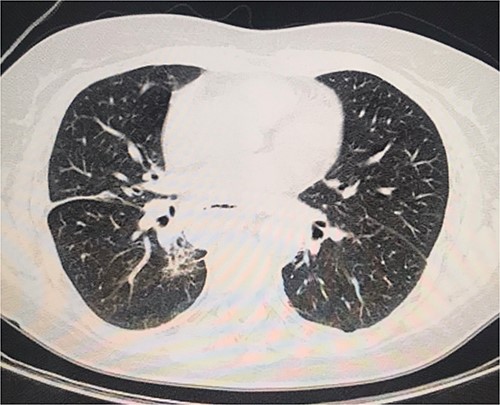

On the second day postoperatively, the patient presented with dyspnea and fatigue; a new chest CT evidenced a hydropneumothorax on the left (Fig. 3). Water-seal chest drainage was performed, with an adequate re-expansion despite the chronicity of the hernia and improvement in ventilatory parameters and symptoms (Fig. 4). She was discharged after 9 days of hospitalization. Currently, she is doing well with a satisfactory response to treatment.